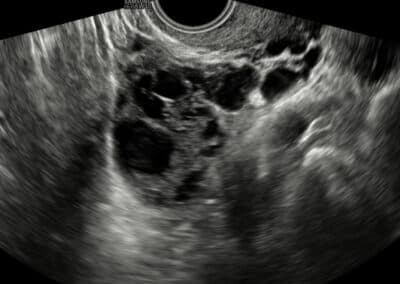

Ultrasound examination of the ovary